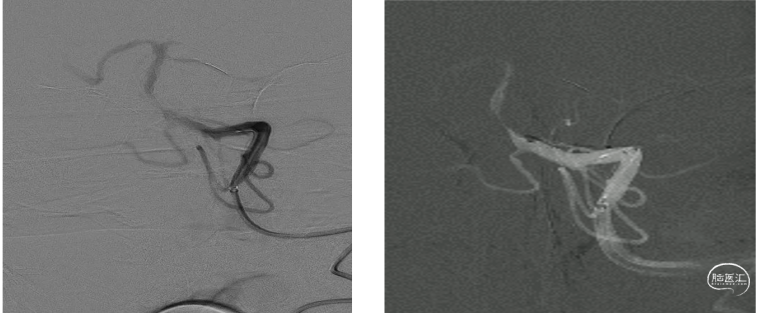

核磁显示:右侧内囊梗塞,大脑中动脉皮层段多发点状低灌注改变。MRA显示右侧大脑中动脉M1段起始部以远未显影,考虑闭塞。

脑血管造影显示:M1起始部以远末显影,大脑前和大脑后动脉通过软膜动脉代偿。

结合影像评估考虑ICAS病变可能性大。

颅内支持导管到达C5段由于血管迂曲成环难以上行。微导丝在C6段形成回头弯顺利到达M2段,Fastunnel输送型球囊扩张导管到达M分叉部。撤出微导丝,微造影显示Ml1分叉以远血流通畅,真实球囊扩张导管在M1段真腔内。

再次球囊扩张:再次将球囊扩张导管置于M1段,在6个大气压(命名压)下扩张导管,泄压后回撤导管造影,右侧大脑中动脉全程血流通畅达3级,远端未见明确血栓逃逸。M1段毛糙,考虑残余狭窄约40%。术中推注替罗非班10mL,撤出导管系统造影大脑中动脉全程血流通畅。